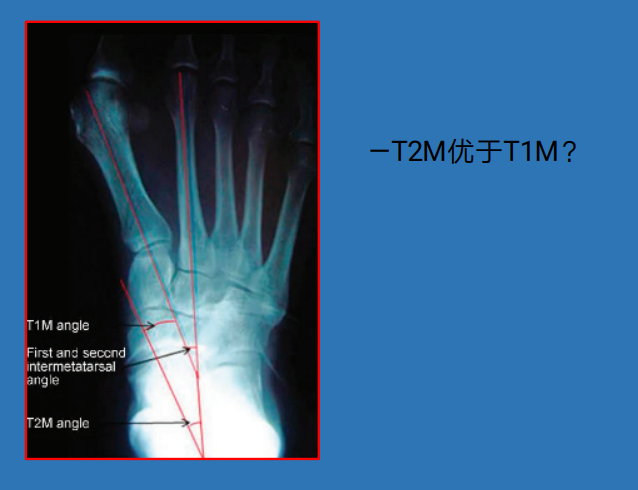

21 前足—拇外翻

拇外翻角Hallux valgus angle,HVA(metatarsophalangeal angle,MTP-1)

正常 < 15°

轻度 < 20°

中度 20°~40°

重度 > 40°

第一、二跖骨间角Intermetatarsalangle,IM 1-2

正常 < 9°

轻度 9°~11°

中度 11°~16°

重度 > 16°

跖骨远端关节角(DMAA)正常<8°